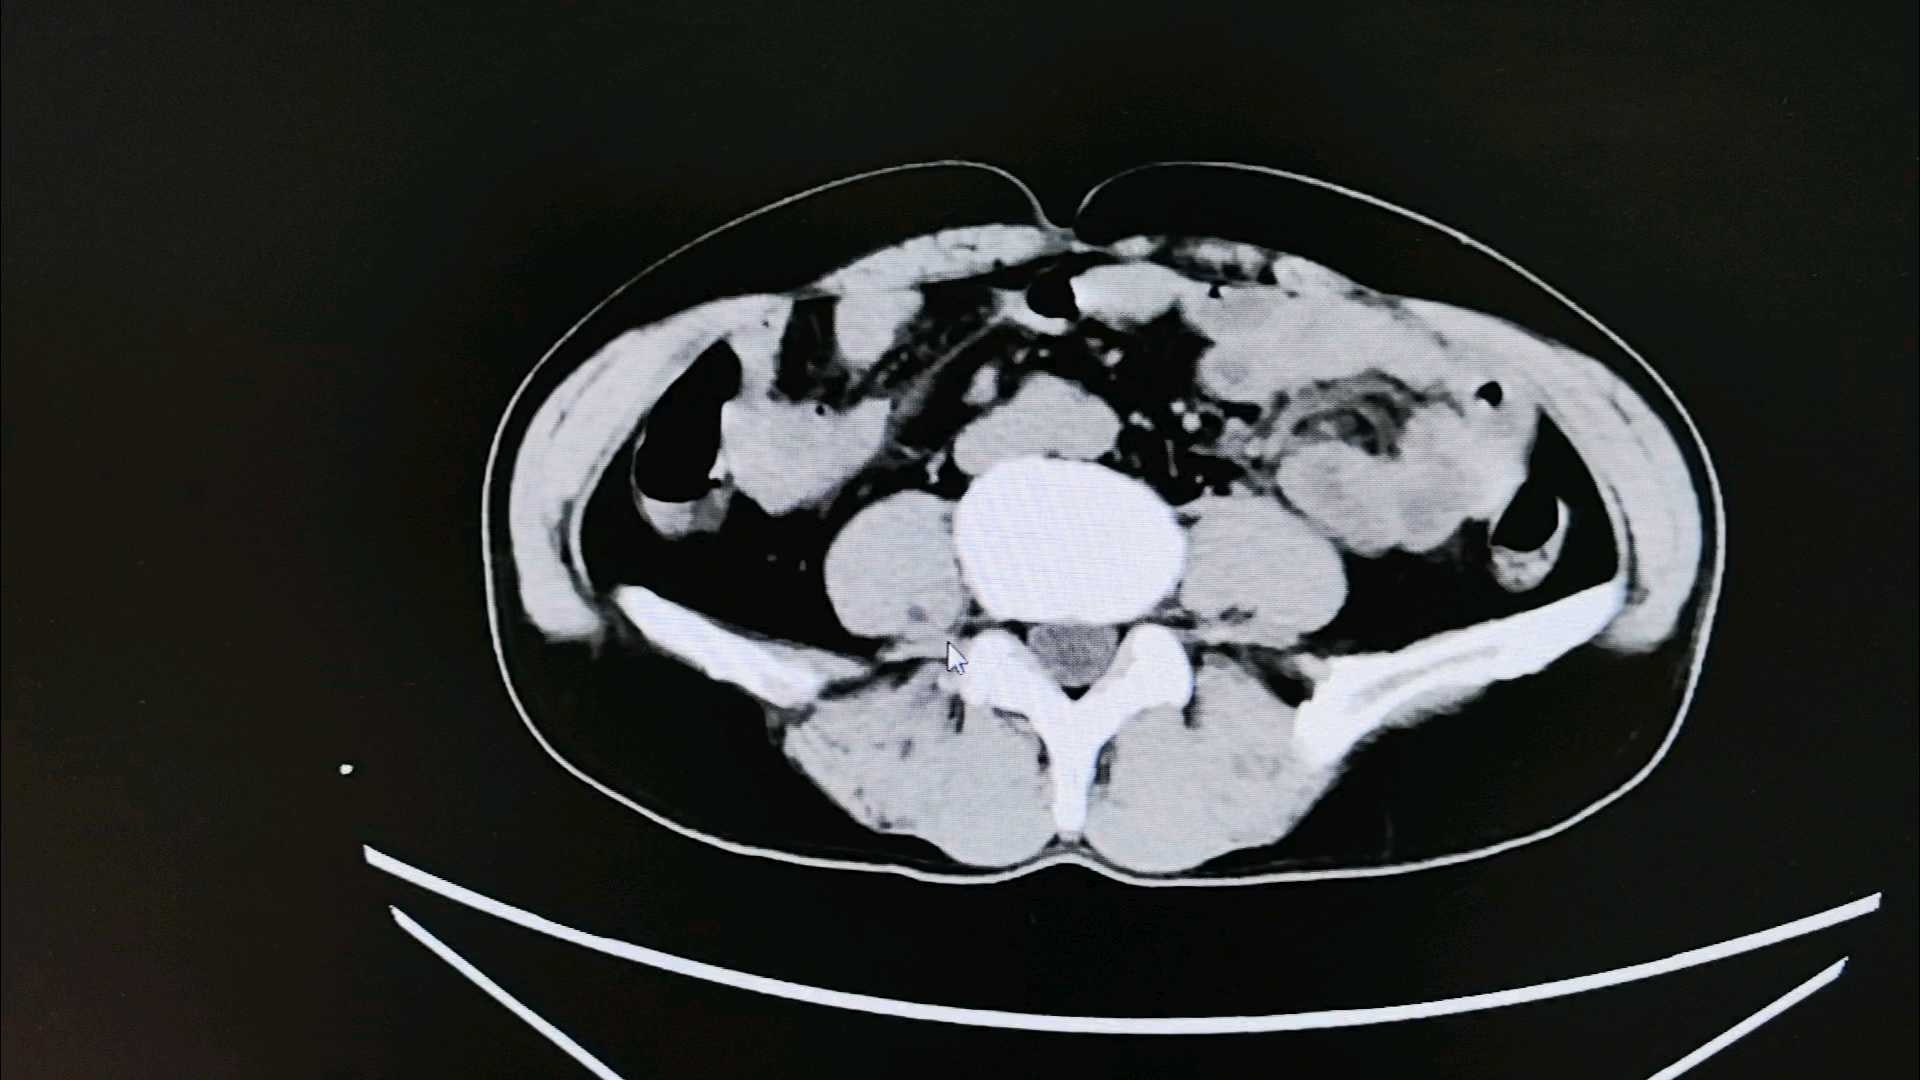

5、复查血常规和CT情况:

已经经伤口留置胃管,后复查的CT片,可见引流管经过右侧精囊腺,考虑精囊腺损伤。但是没有大出血。准备请泌尿科会诊,指导是否需要后续治疗。

【临床诊断】:会阴木棍刺入伤,右侧精囊腺损伤。